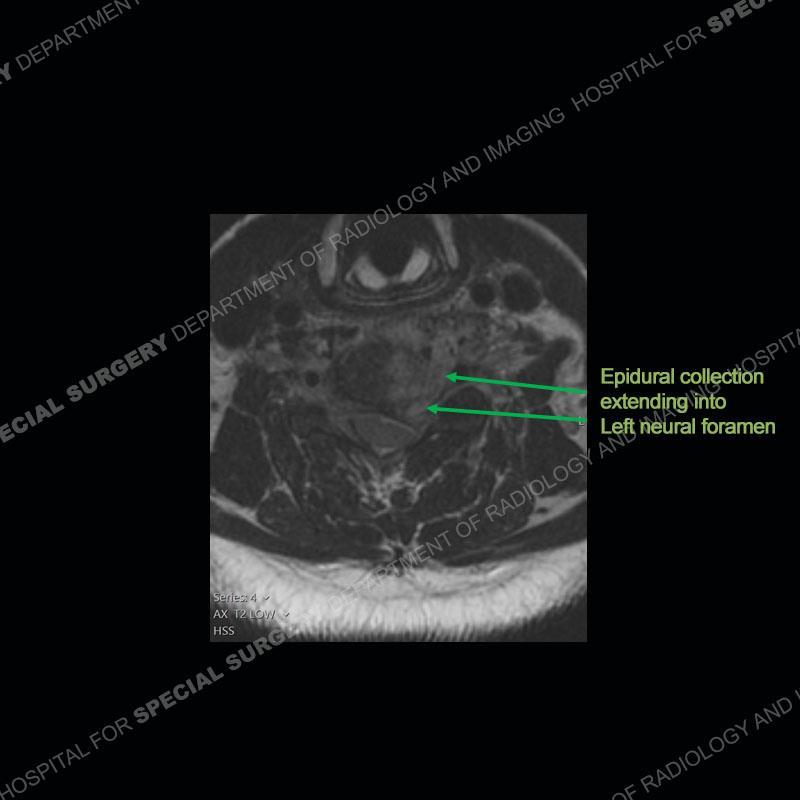

The radiographs demonstrate a prevertebral soft tissue fullness centered at C5-C6 that persists even on extension. There is a slight loss of disc height at C5-C6. The CT more readily shows the prevertebral soft tissue swelling at C5C6 where there is a punctate focus of gas. On the MRI, there is a marked amount of edema and a heterogeneous collection in the prevertebral soft tissue at C5-C6. Edema is present of the C5 and C6 vertebral bodies with a loss of the normal architecture about the disc space. A heterogeneous epidural collection has formed that causes compression of the spinal cord asymmetric to the left side and also precipitates severe left sided neural foraminal stenosis.